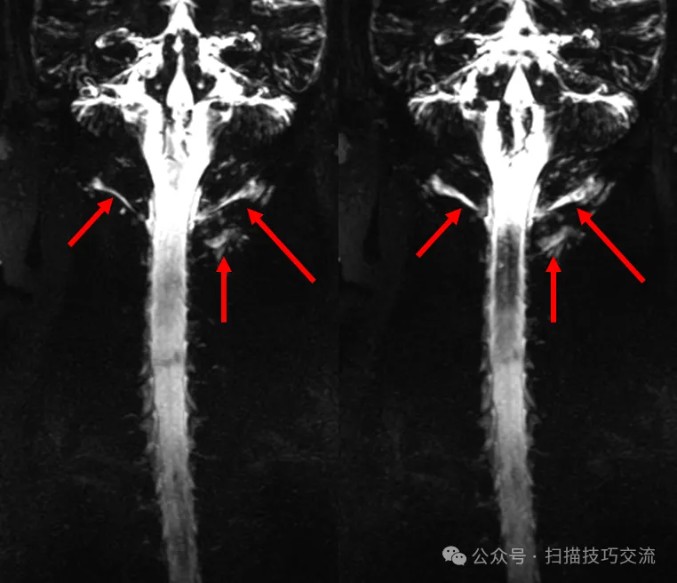

加个COR 2D MRM对照一下。扫描参数界面:

有点感觉了吧。

来都来了,再加个3D MRM看一下,